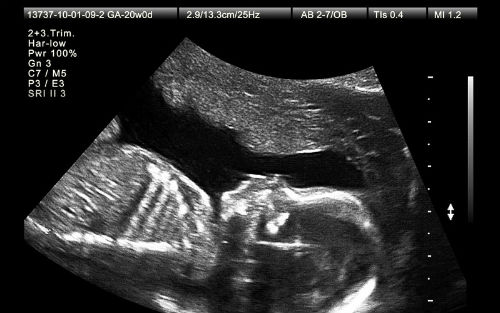

超声波往往被用于产前筛查。怀孕妇女可以选择的几种产前筛查中,这只是其中一种。